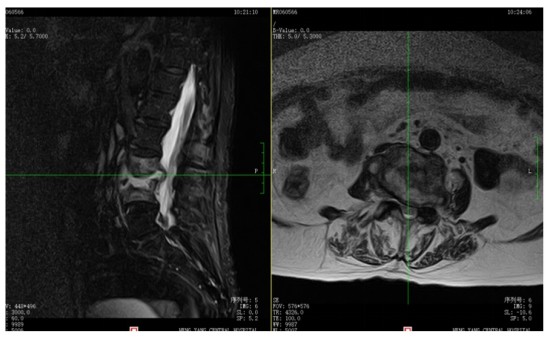

為解決老人病痛,脊柱外科錢軍博士團隊對其進行了詳細的查體以及全面細致的評估,診斷為L3、4脊柱結(jié)核伴病理性骨折、椎旁膿腫,患者腰部疼痛癥狀逐漸加重,病灶已經(jīng)壓迫神經(jīng)引起了截癱。